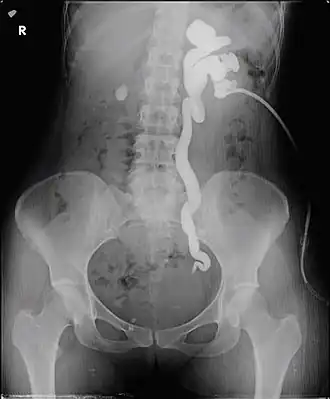

Antegrade pyelogram of grade III hydronephrosis with obstruction at the ureterovesical junction due to bladder endometriosis in a 29 year old female. The tip of the nephrostomy is located in an inferior calyx.

Antegrade pyelography is the procedure used to visualize the upper collecting system of the urinary tract, i.e., kidney and ureter. It is done in cases where excretory or retrograde pyelography has failed or contraindicated, or when a nephrostomy tube is in place or delineation of upper tract is desired. It is commonly used to diagnose upper tract obstruction, hydronephrosis, and ureteropelvic junction obstruction. In this, radiocontrast dye is injected into the renal pelvis and X-rays are taken. It provides detailed anatomy of the upper collecting system. As it is an invasive procedure, it is chosen when other non-invasive tests are non confirmatory or contraindicated and patient monitoring is required prior and after the procedure.[11][12]